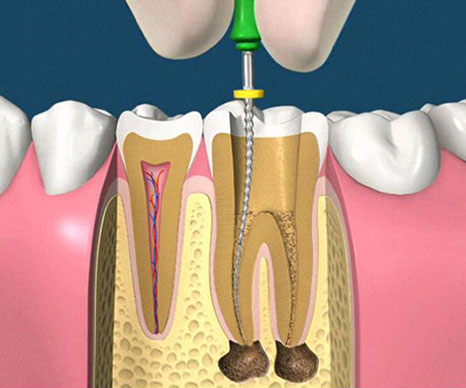

• accesso alla camera pulpare mediante frese diamantate

• asportazione della polpa e sagomatura dello spazio endodontico con strumenti meccanici (in nichel-titanio), con l'ausilio della detersione del canale radicolare (acqua ossigenata, ipoclorito di Sodio, calcio-chelanti)

• otturazione di tutto l'endodonto mediante materiali termoplastici (guttaperca) e cementi biocompatibili